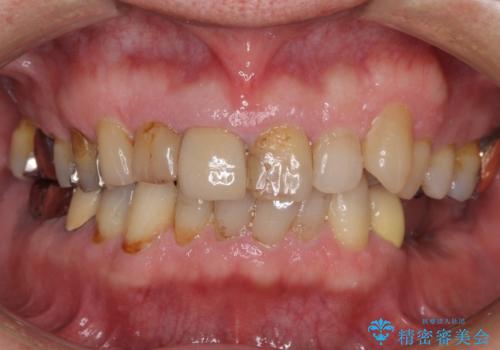

- 前歯がぐらつくことを主訴にご来院された患者様です。ご本人は抜歯と考えており、インプラント以外の治療をご希望でした。しかしながらぐらついていた原因は、古い差し歯が取れかけていたことでした。

遠方から通院されること、仕事上短期間で治療したいとのことを考慮して、残っている歯はかなり小さいものの、保存すべきと判断して当日処置から行いました。

西日本から新幹線でご来院された患者様です。前歯は都内の医院でやりたいとのことで、はるばる通院してくださいました。通院回数が最小限になるよう工夫しました(1回あたりの時間は長くなります)。

残っている歯が小さいと、差し歯はぐらつきやすくなりますが、その形態によっては抜歯を回避できることがあります。